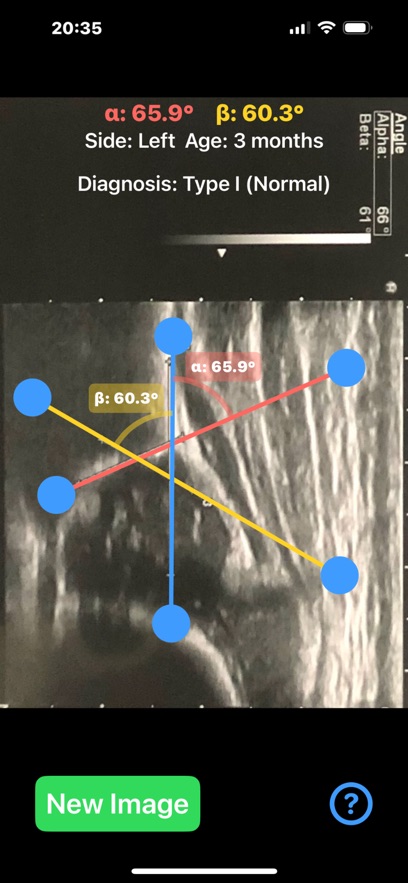

Ultrasonography, rather than X-ray, is the preferred method for diagnosing DDH in infants, especially under the age of 6 months. Ultrasound provides a non-invasive and radiation-free way to visualize the soft tissues, cartilage, and bones in real time. The Graf method is the most widely used technique, where two critical angles—alpha (α) and beta (β)—are measured to assess the development of the acetabulum and classify the hip's condition.This application is designed to aid healthcare professionals—especially radiologists, orthopaedic surgeons—in evaluating DDH by calculating the alpha (α) and beta (β) angles quickl from saved ultrasound images of the patient hip.

Provide instant visual feedback by color-coding the angles:Alpha angle (α): red, Beta angle (β): yellow. Automatically also classify the hip joint based on the Graf method Type I,Type IIa/b,Type IIc,Type III, helping clinicians to have a quick glimpse and visualise the relationship between the angles ,real time.Healthcare professionals, particularly in busy departments, can save significant time by quickly loading ultrasound images and automating angle calculations, identify abnormal hips on the go . App can also be used as a training tool for medical students, residents, and junior clinicians, teaching them how to recognise key landmarks, make accurate measurements, and classify DDH using ultrasound images. By rapid visually displaying the measurements on the screen and generating easy-to-understand images, app helps clinicians explain the condition and its severity to parents.

App offers α and β angle measurement by dragging points on the ultrasound image to key anatomical landmarks, forming lines that define the acetabular roof and cartilaginous roof. The app automatically calculates the angles and classifies the hip condition based on these measurements in real-time.

Important feedback that help allow the user to adjust draggable points and see immediate changes in the angle values helping to fine-tune the position of the lines and target the preferred anatomical landmarks of the ultrasound image more efficiently. User-friendly interface, and reliable classification system based on Graf’s classification that streamline the diagnostic process, and improved overall workflow in clinical practice.